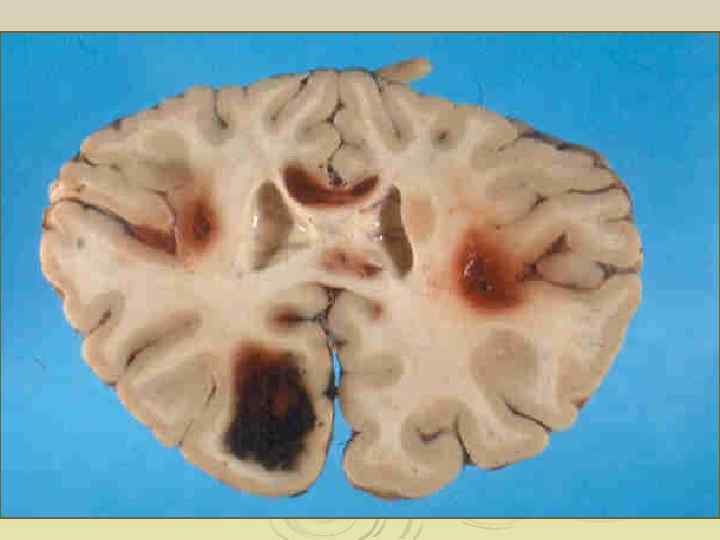

Вторичные изменения при лейкозах • анемический синдром • геморрагический синдром • интоксикационнный синдром • иммунодефицит • гиперпластический синдром • системные нарушения микроциркуляции (дисфункция эндотелия, лейкостаз и т. д. ) • метаболические нарушения

Геморрагический синдром